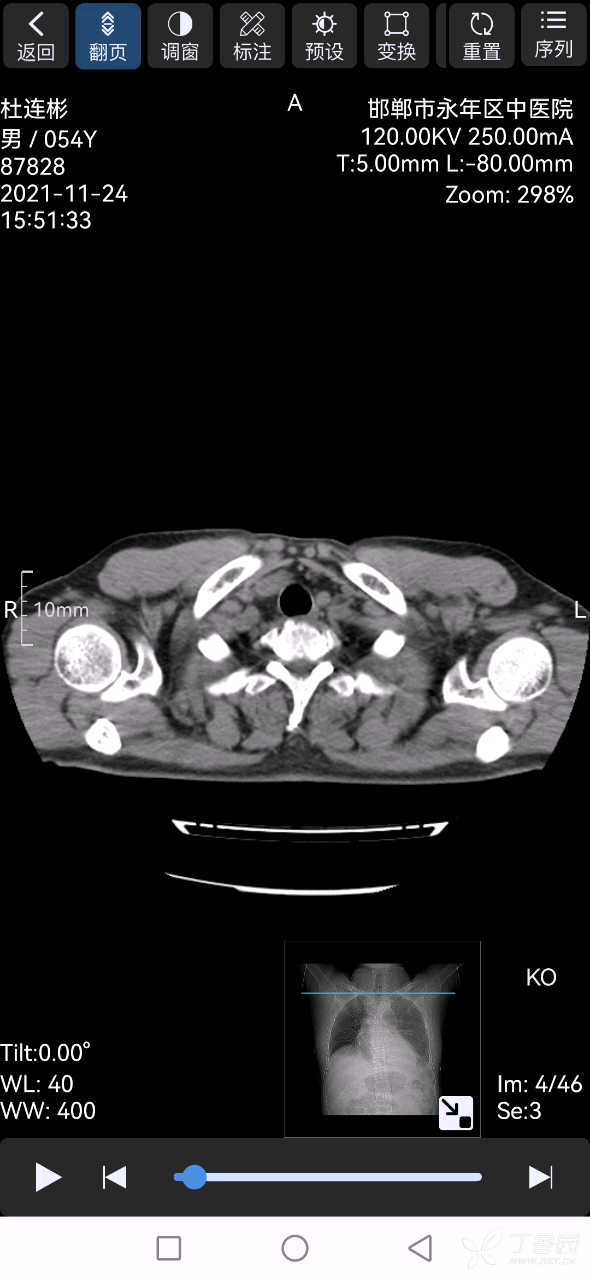

下面是第一天和第七天的CT。

患者男性,54岁,目前胸外伤7天。目前疼痛减轻,脱氧状态下胸闷气短明显,无发烧。基本无咳嗽咳痰。因经济原因患者要求保守治疗,我是基层医生,胸外科病人遇到的少,请问胸外科的老师们接下来需要怎么处理?需要注意什么?拜谢!!!